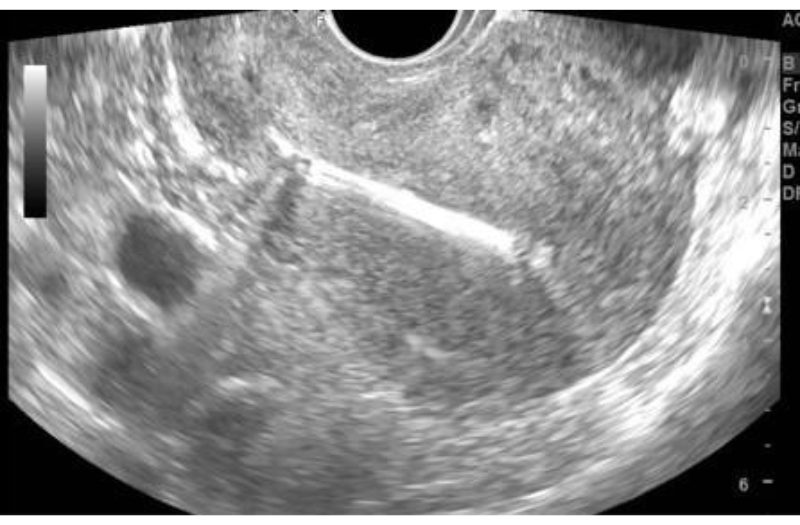

Xét nghiệm này chỉ có giá trị sàng lọc, không có giá trị chẩn đoán. Do vậy bạn vẫn kết hợp với siêu âm 4D khảo sát hình thái thai nhi, tiền sử thai sản, tiền sử gia đình... Từ đó bác sỹ chuyên khoa sẽ tư vấn cho bạn nên lựa chọn phương pháp sàng lọc không xâm lấn NIPT hoặc chọc ối để chẩn đoán.